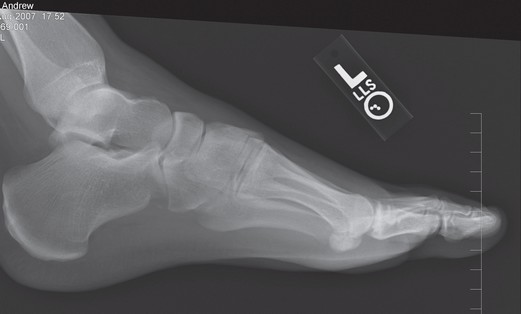

Plantar fascia calcification can occur in the setting of plantar fasciitis 1 or rarely as a sequelae of prior steroid injection 2. Heel spurs on the bottom of the heel are often associated with both plantar fasciitis and plantar bursitis. Plantar fasciitis is a disorder of the insertion of the plantar fascia as it inserts on the calcaneus (heel bone), causing pain in. Plantar fasciitis is by far the most common cause of heel pain. A doctor will usually suspect you have plantar fasciitis based on your symptoms and a physical exam. Plantar fasciitis is usually diagnosed via a medical history, discussion of symptoms and physical examination.

Several findings suggestive of plantar fasciitis can be detected on conventional radiographs. We use ultrasound in our office. It can be quite convincing because theres this extra pointy piece of bone right in the area where your pain is, but the recent research has shown that this is actually not the case. Plantar fasciitis is a clinical diagnosis and is often combined with some form of imaging to validate the diagnosis. Calcific enthesopathy of the achilles tendon is also seen (open arrow) (a).on ultrasound, plantar fasciitis presents with pf.

Once you have a positive plantar fasciitis diagnosis, there are numerous treatment options to. The best way to tell is with an ultrasound image of the bottom of the heel. Plantar fasciitis is a clinical diagnosis and is often combined with some form of imaging to validate the diagnosis. Several findings suggestive of plantar fasciitis can be detected on conventional radiographs. In addition to stress fractures, some mistake gout, achilles tendinitis and other painful conditions for plantar fasciitis, resulting in them suffering unnecessarily while treating the wrong problem.

Ultrasound images clearly show the fluid sac. Plantar fasciitis is a disorder of the insertion of the plantar fascia as it inserts on the calcaneus (heel bone), causing pain in. This will help discover any abnormality, such as a stress fracture or a heel spur. It’s important to understand that heel spurs do not cause pain and you won’t automatically need surgery just because you have a heel spur. Despite this, plain radiography should not be used to make a diagnosis of plantar fasciitis without knowledge of clinical history or physical examination findings.

You will not be able to tell the difference between plantar fasciitis and a heel spur. They can, however, be very valuable in ruling out or confirming a stress fracture. The symptoms for plantar fasciitis and heel spur are the same. Several findings suggestive of plantar fasciitis can be detected on conventional radiographs. The first doctor you will see when you think you have plantar fasciitis is your general practitioner.